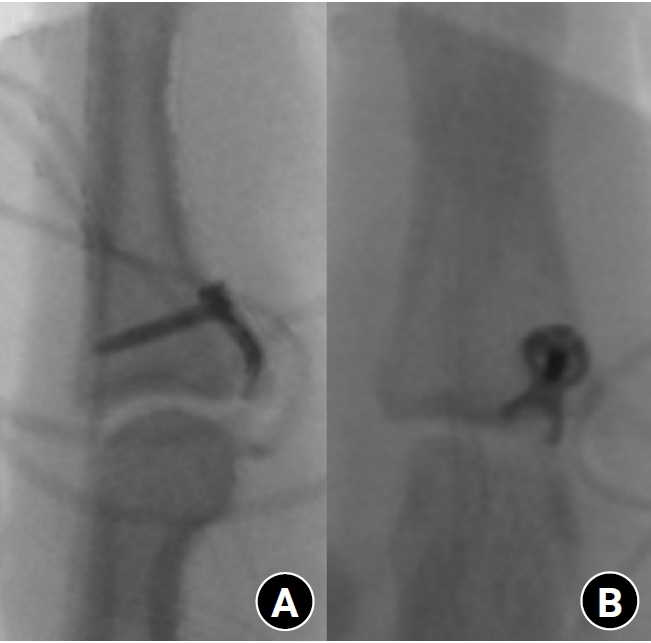

Fig. 3.

Radiographs after hook plate fixation. (A) Lateral view. (B) Anteroposterior view showing the hook plate crossing the fracture line and secured with a distal screw.

The surgical procedure was similar to that described by Kang et al. [3] and Thirumalai et al. [4]. All procedures were performed under general or regional anesthesia. A volar Bruner or zigzag incision was made to expose the PIP joint. The flexor tendon was retracted, and the volar plate was identified between the flexor tendons and the collateral ligament. The fracture fragment was visualized and meticulous dissection was performed to preserve soft-tissue attachments and vascularity. The hook plate was fabricated from a 1.5-mm modular hand system titanium plate (Synthes). A two- or three-hole plate was modified into a hook plate depending on the requirement. The cut ends of the plate were bent into hooks (Fig. 1). Anatomical reduction of the fracture fragment was successfully achieved using the hook plates (Fig. 2). Subsequently, the hooks were passed through these slips around the edge of the joint at the distal edge of the fracture fragment. They grabbed onto the lip of the articular surface in an area that does not interfere with joint function. Then, the hooks were used to control and reduce the fracture fragment. A 0.9-mm K-wire could be used to help reduce and hold the fracture fragment temporarily while applying the plate. The plate crossed the fracture line and was fixed with a single screw distal to the fracture (Fig. 3). Fixation stability was confirmed by passively moving the joint through a full passive ROM under C-arm fluoroscopy. After surgery, the finger was immobilized in a functional position using a dorsal blocking splint for one week. Gradual active and passive ROM exercises were initiated thereafter under protective splinting, and unrestricted use was permitted after radiographic confirmation of bone union.

The surgical technique used in this study, which is similar to that of Kang et al. [3] and Thirumalai et al. [4], allowed for the anatomical reduction of the fracture fragments and precise placement of the hook plate. The hook plate, which was fabricated from a 1.5-mm modular hand system titanium plate, provided the necessary stability by converting tensile forces into compressive forces across the fracture site.